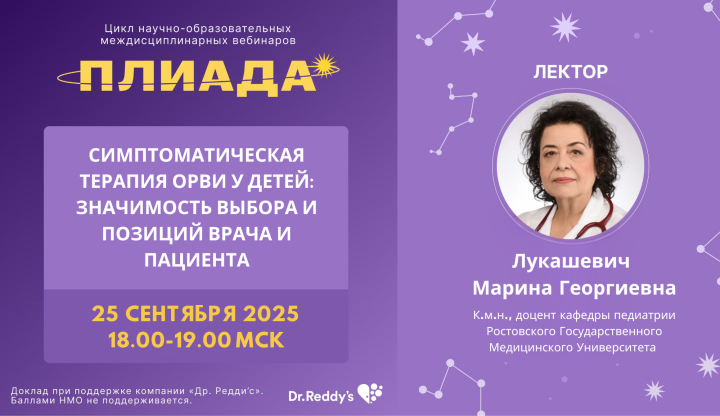

Симптоматическая терапия ОРВИ: Значимость выбора и...

Уважаемые коллеги! Приглашаем вас на вебинар «Симптоматическая терапия ОРВИ: Значимость выбора и позиций врача и пациента». В рамках...

60 мин